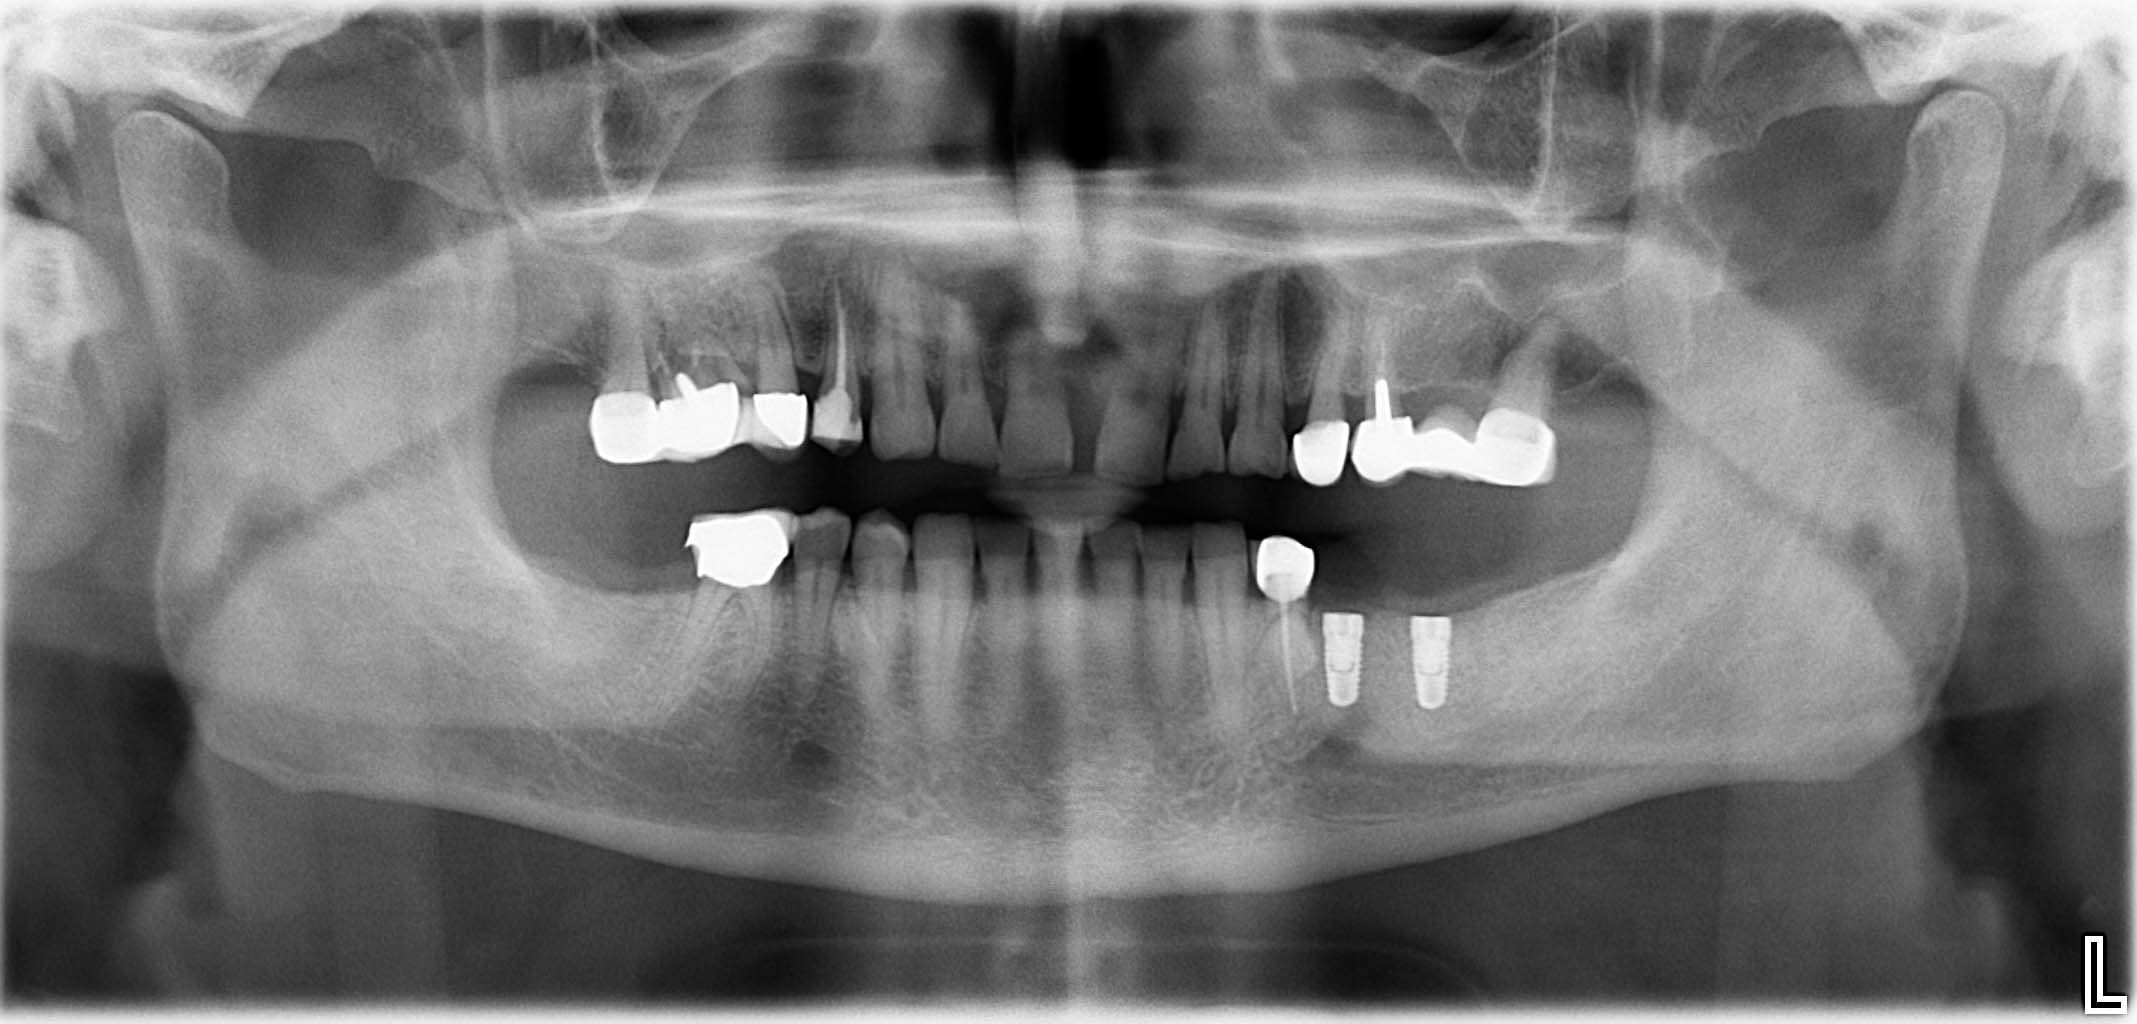

Erfolgreich implantierte Patientenfälle (klinische Fotos)